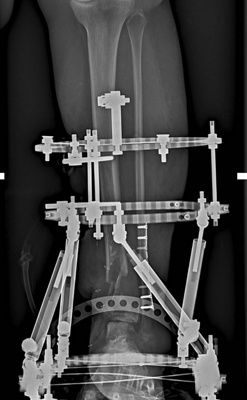

When patients have tibial (shin) bone loss, reconstructing the bone can be a difficult and lengthy process.  Often, the bone is regrown with the help of an external fixator – a scaffold that can be worn on the outside of one’s hand, arm, foot, or leg to help keep bones in place so they can heal and grow.

So just how does the Eiffel Tower procedure work? “We conduct a CT scan of the injured limb and look at the shape of the bone that’s missing,” explains Dr Birkholtz. “We model that in three dimensions and in consultation with a biomedical engineer, and through the use of a 3D printer, we create a titanium truss cage that looks like the Eiffel Tower. The cage is then fixed to the surrounding bone and tissue. It’s basically a structure that takes over some of the function of the bone but because we pack the structure full of bone graft, it incorporates into the bone as well, becoming a permanent fixture and replacing that segment of bone that is missing.”

It’s a single procedure that solves a very complex problem in a single operation. “Other reconstructive options entail multiple procedures, operations and often long recovery time,” says Dr Birkholtz. “With this procedure, it takes six to eight weeks to hold weight again – with reasonable functionality in up to three months.”